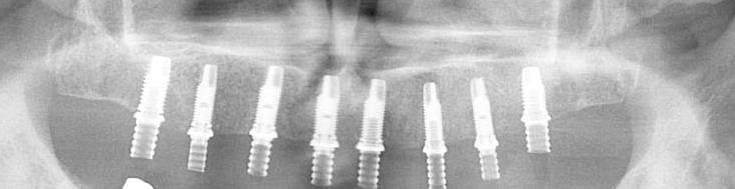

诚和植牙優勢

1. 最新3D高科技醫療設備

本院设备最新植牙專用3D (CBCT) 体影像設備,可決定最佳的植入位置 角度,大幅度提高植牙的安全性, 成 率, 與準確度。

4. NYU 大學植牙醫師為您診治

本院植牙專師陳賜恆醫師具多張植牙證照與專利 ,包括紐約大學植牙部門的Implant Fellowship,能讓您安心與放心。 經驗豐富, 超過數千個成功案例; 接近100%成功率。

真实病例